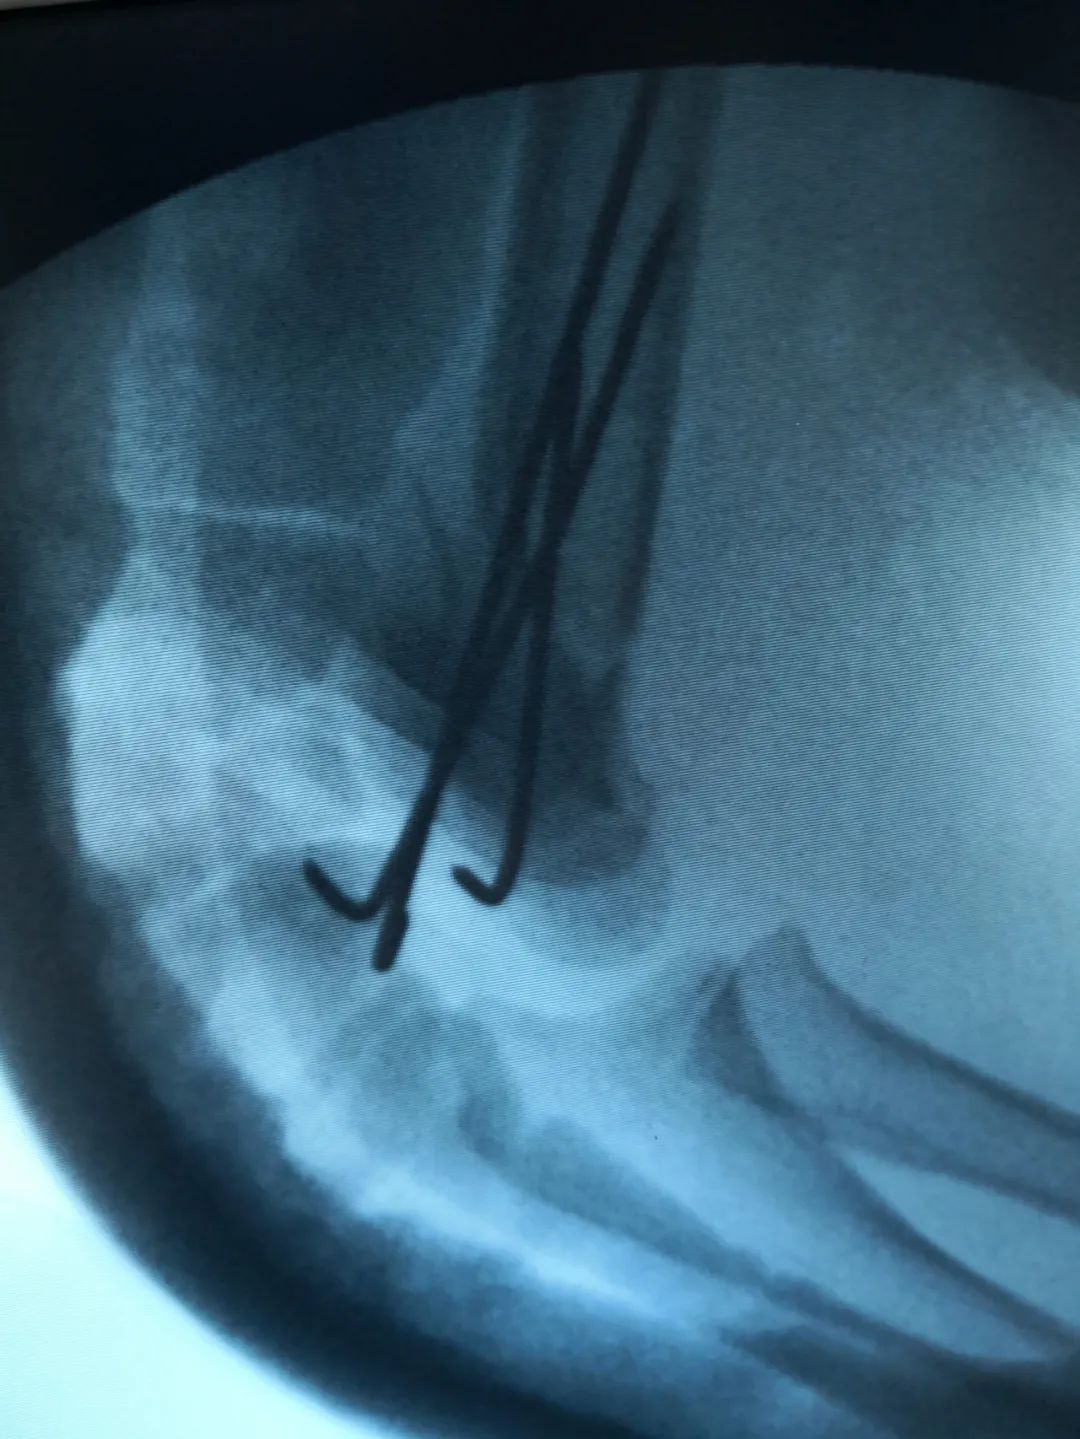

刘法银医生介绍称,经检查,童童诊断为右侧肱骨髁上骨折,软组织挫伤重,伴桡神经损伤,给予‘桡神经探查术+切开复位内固定术’。

“对于另外2例骨折患儿,因未造成神经损伤,给予C臂透视下手法复位闭合穿针内固定手术,不用切口,创伤小,恢复快,术后四周门诊拔出钢钉,免除二次手术取内固定。”刘医生说道。